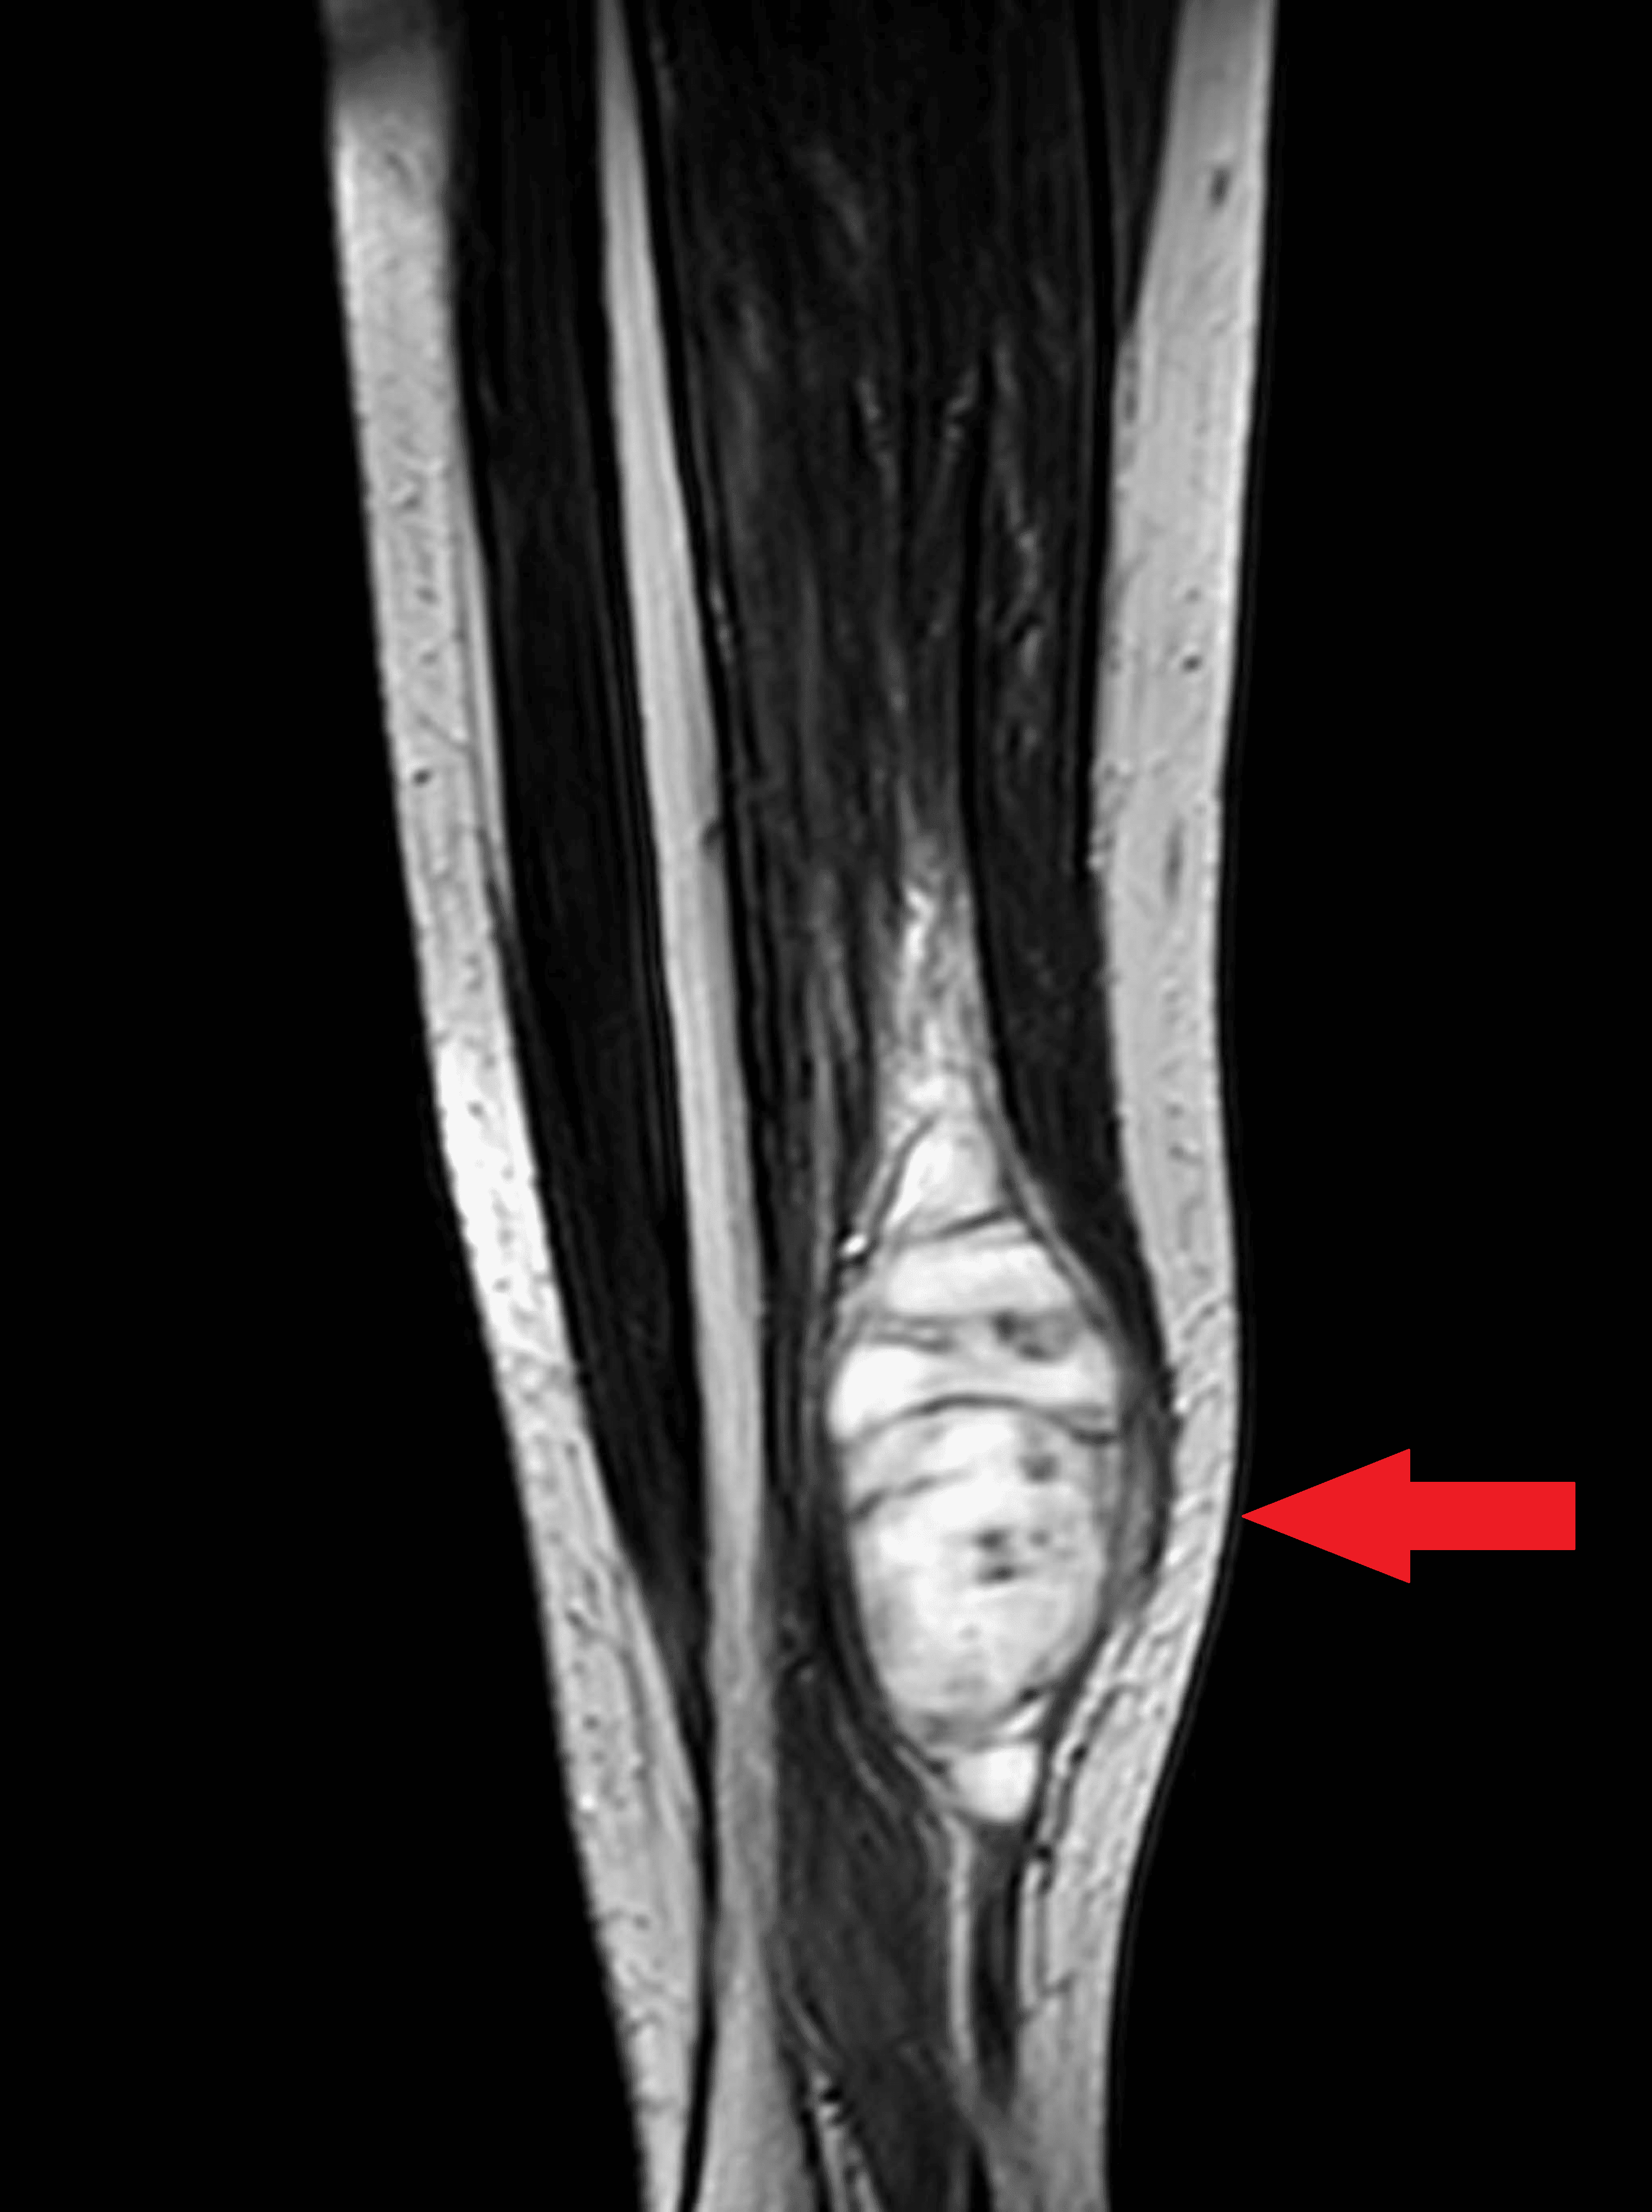

Cureus Chronic Lower Limb Pain Unveiling a Rare Case of Spindle Cell Soft Tissue A Spindle Cell Lesion Knee — synovial sarcoma is a rare type of cancer that tends to occur near large joints, mainly the knees. spindle cell tumor and spindle cell sarcoma are descriptive names used when tumor cells look long and narrow under the. Monophasic synovial sarcoma composed of spindle cells and is. — spindle cells are quite uniform and arranged in. Spindle Cell Lesion Knee.

Cureus Rotationplasty for Spindle Cell Tumor of Tibia Spindle Cell Lesion Knee — synovial sarcoma is a rare type of cancer that tends to occur near large joints, mainly the knees. Monophasic synovial sarcoma composed of spindle cells and is. spindle cell tumor and spindle cell sarcoma are descriptive names used when tumor cells look long and narrow under the. When viewed under a microscope, the cancerous cells appear long. Spindle Cell Lesion Knee.